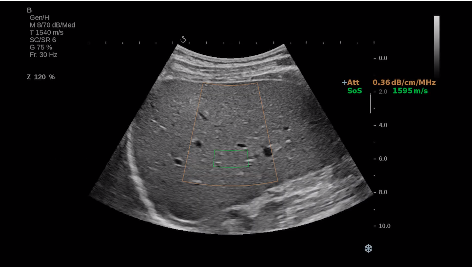

法國聲科影像(SuperSonic Imagine,SSI. Euroniex:FR0010526814)近日發(fā)表公告,宣布其研發(fā)的新一代“極速”超聲成像平臺(UltraFast Imaging),首次實現(xiàn)了肝臟的多項超聲定量評估新指標同步檢測,包括:Att PLUS,SSp PLUS和Vi PLUS等,基本涵蓋肝臟相關病理變化指征的如纖維化、脂肪變、炎癥等。據(jù)悉,此多項新技術新將搭載于新Aixplorer系列E超系統(tǒng)。

E超相關技術已被多項多中心大樣本研究證實對于肝纖維化無創(chuàng)評估有重要意義,同時也可全面應用于乳腺、甲狀腺、肝臟、前列腺、肌骨、婦科等全身各組織器官的定量評估和鑒別診斷。在慢性肝臟方面,聲科E超的肝臟相關定量診斷技術集,于2018年獲得美國FDA認證,成為FDA歷史上首次獲批的單病種超聲全面定量解決方案。